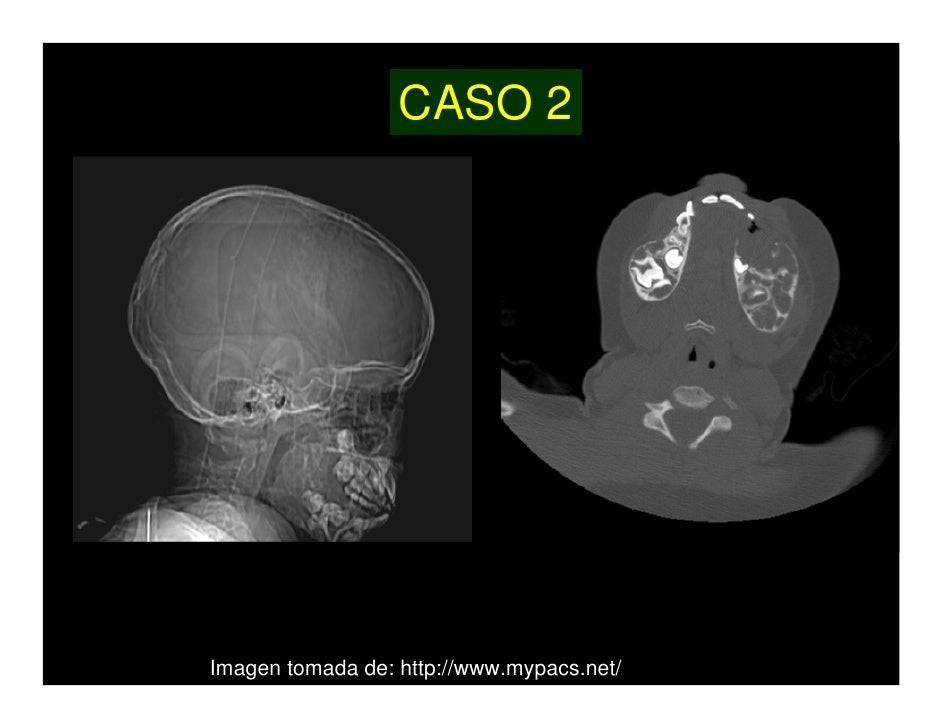

El querubismo es una enfermedad rara de origen genético y herencia autosómica dominante, que se caracteriza por un crecimiento anormal de varios huesos de la cara, principalmente el maxilar inferior y maxilar superior. Generalmente el trastorno provoca las primeras manifestaciones alrededor de los 4 años y detiene su progresión al final de la adolescencia, desapareciendo lentamente a partir de entonces las deformidades y persistiendo únicamente algunas manifestaciones residuales en la vida adulta. Se ha comprobado que la enfermedad se debe a una mutación en el gen SH3BP2 localizado en el cromosoma 4pl6.3, el cual codifica una proteína constituida por 561 aminoácidos.

El trastorno origina un aspecto característico de la cara que recuerda a las representaciones de querubines, de donde toma su nombre. Existe aumento de tamaño bilateral de la mandíbula asociado a tumores quísticos no malignos. Además de las deformidades faciales que tienen importancia desde el punto de vista estético y psicológico, pueden existir complicaciones, entre ellas pérdida de visión por neuropatía óptica, obstrucción de vías aéreas superiores, apnea del sueño, trastornos del lenguaje y dificultad para la masticación por alteraciones en la aparición y desarrollo de las piezas dentales.[1] [2][3]